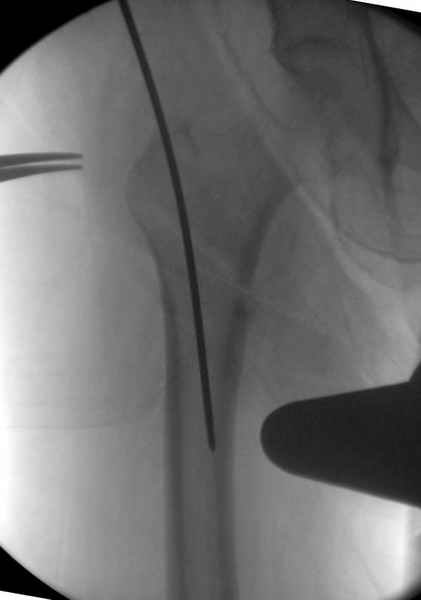

Мы получили испытательный вариант инструментария для пробы, хотя компания объявила, но ещё не для широкой публики, обещают к сентябрю. За полтора месяца, включая сегодняшнюю, вот уже восьмая операция по счету. Удобный инструментарий, ничего лишнего, научились делать быстро, посмотрим что будет, пока нравится.

Здесь сканнированные снимки импланта и операционные снимки больной.